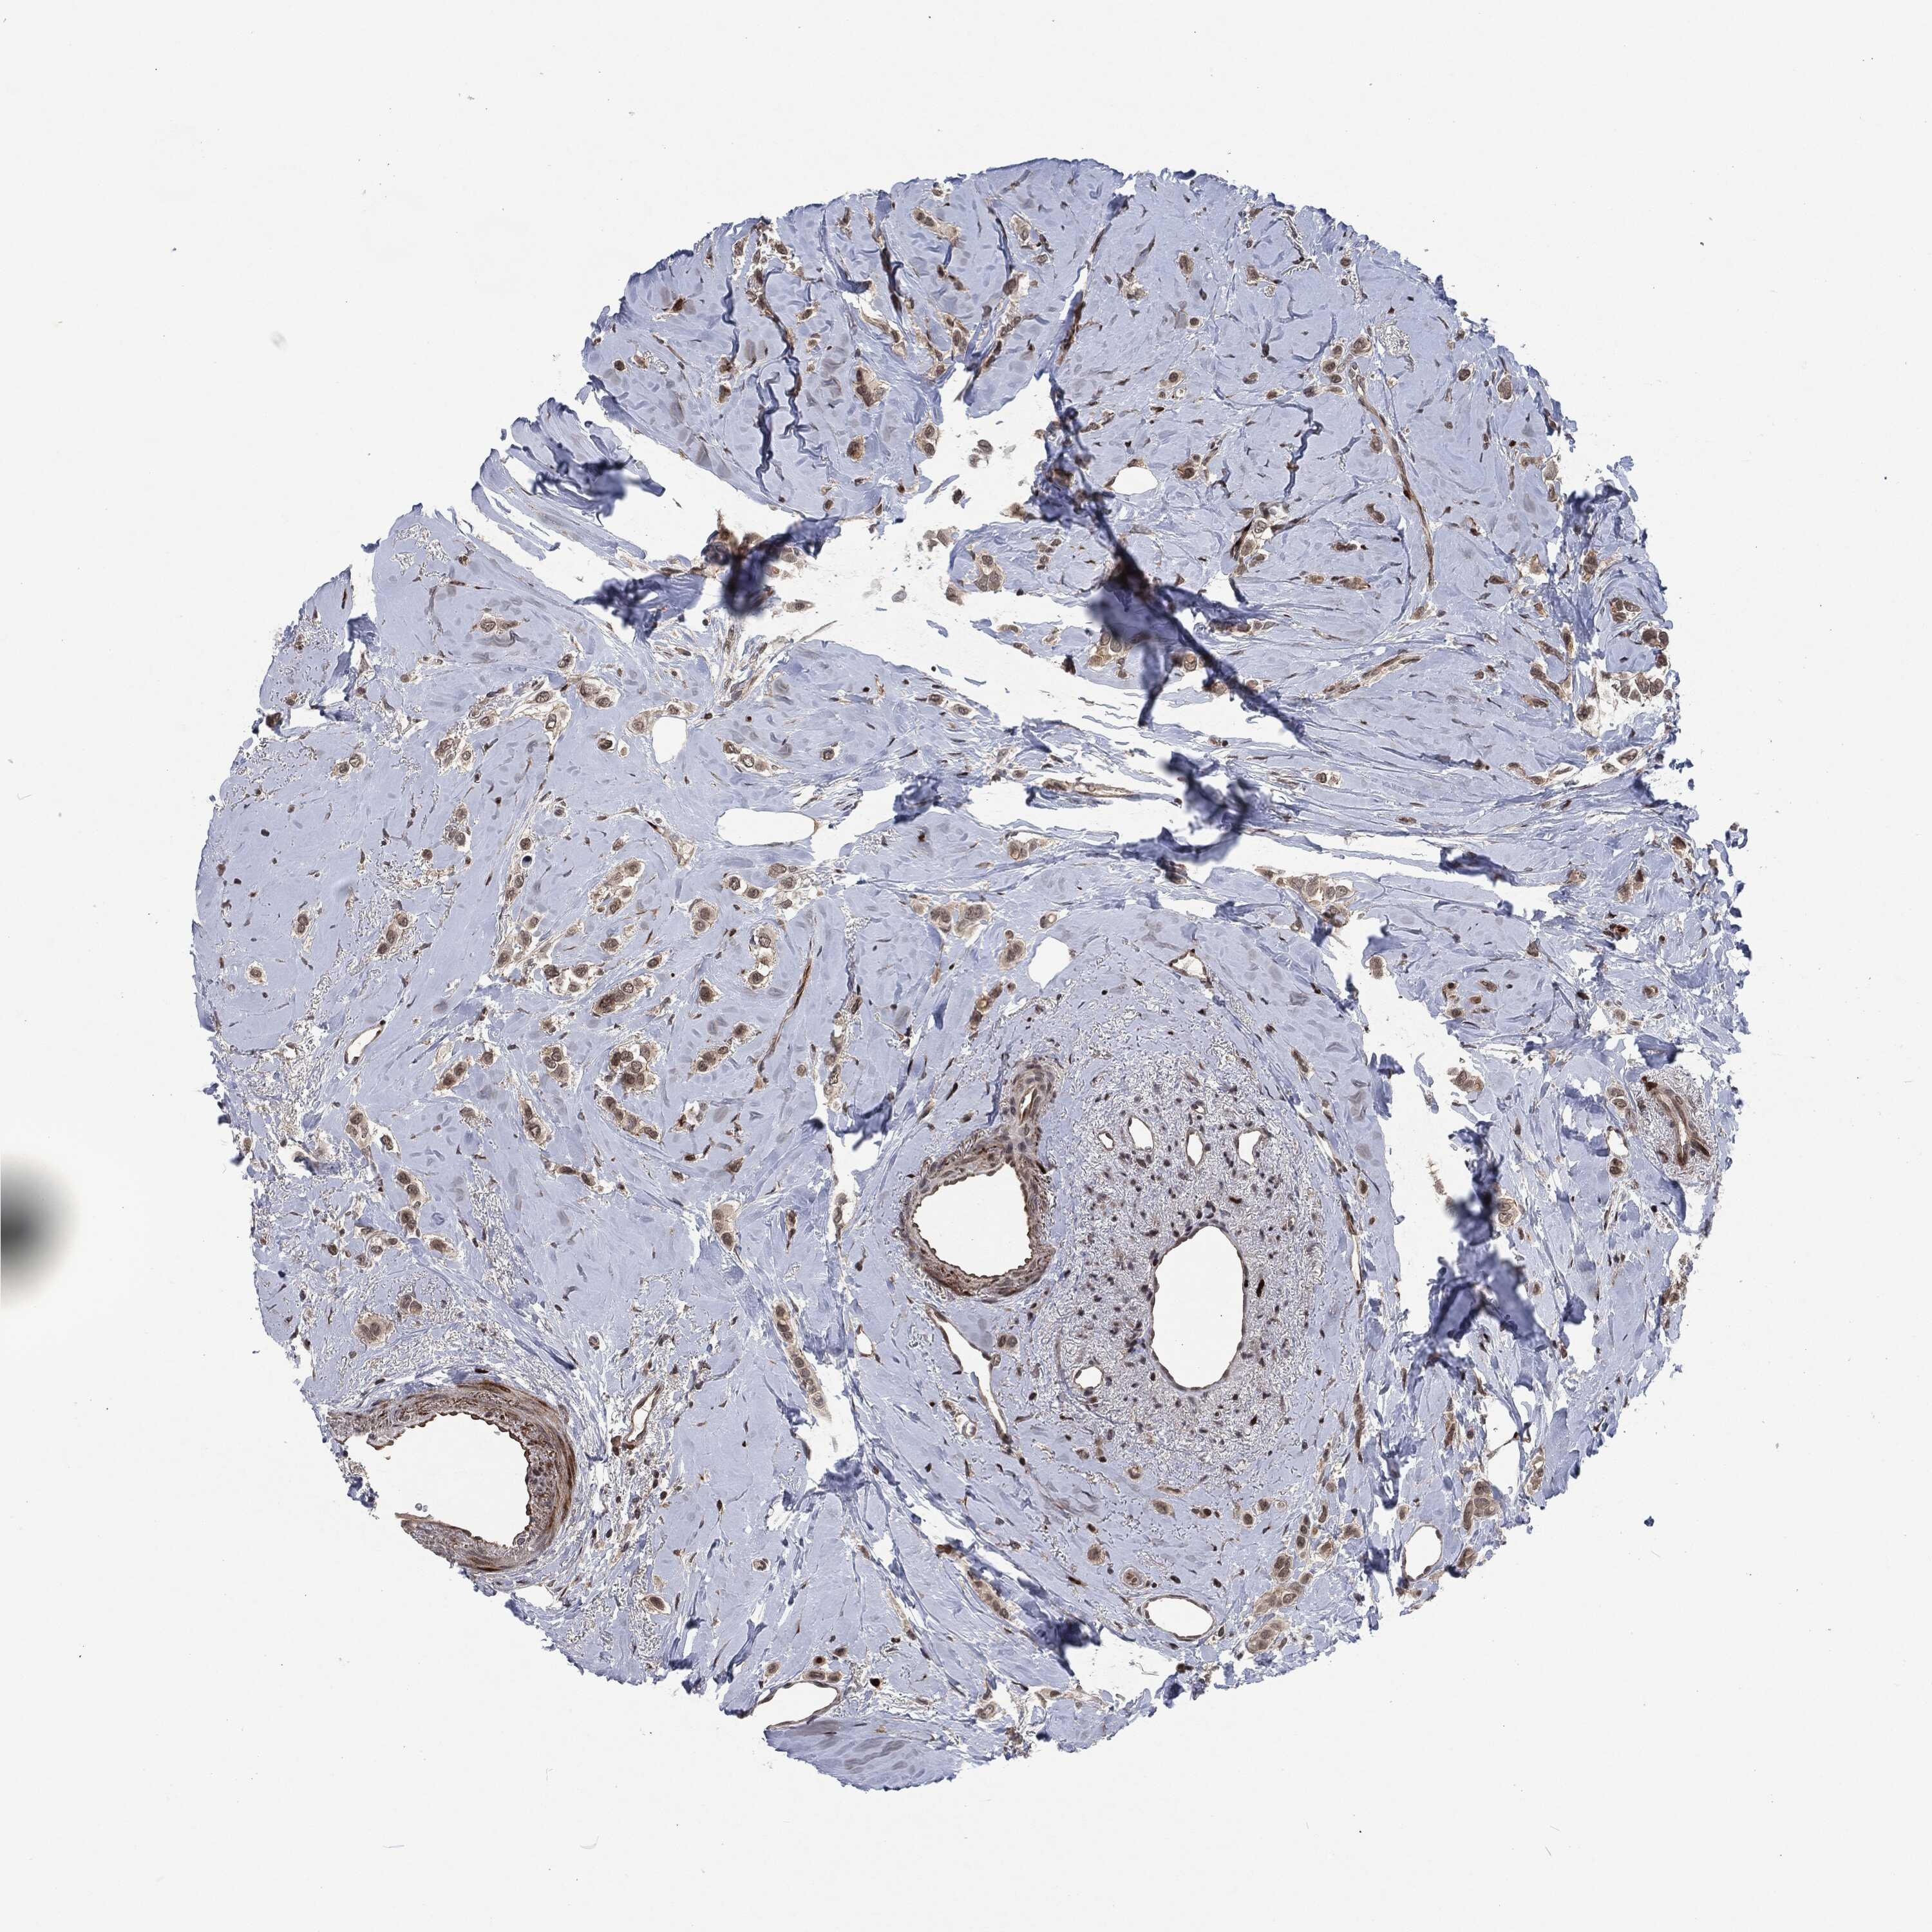

CANCER BREAST CANCER Show tissue menu

BRCA TCGA BRCA VALIDATION PROTEIN EXPRESSION

ANTIBODIES

AND

VALIDATION